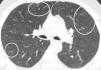

In our case, differential diagnosis was performed for primary (hematopoietic neoplasms with HE) and secondary HES, (helminth infections, allergic reactions, atopic diseases, drug reactions (allergic or toxic), Hodgkin disease, B- or T-cell lymphoma/leukemia, Langerhans cell histiocytosis, indolent systemic mastocytosis, solid tumors/malignancy, allergic bronchopulmonary aspergillosis, chronic inflammatory disorders, autoimmune diseases and lymphoid variant of HES), organ-restricted conditions accompanied by HE (eosinophilic gastrointestinal disorders, eosinophilic pneumonia, dermatologic diseases, etc.) and specific syndromes accompanied by HE (Gleich syndrome, Churg-Strauss syndrome, eosinophilia myalgia syndrome, Hyper-IgE syndrome).1–6 The patient was diagnosed with idiopatic HES after exclusion of all primary and secondary causes and exclusion of other conditions and syndromes. The patient was started on imatinib mesylate therapy with 400mg/day because he did not respond to corticosteroids (CS) and hydroxyurea therapy. The treatment was reduced to a 100mg in the third month of treatment due to normalization of eosinophil levels and disappearance of all complaints. The ground-glass nodules disappeared after 1 year of imatinib treatment (Fig. 1b).

Axial CT image at the same level as in Fig. 1a showing disappearance of ground-glass nodules.